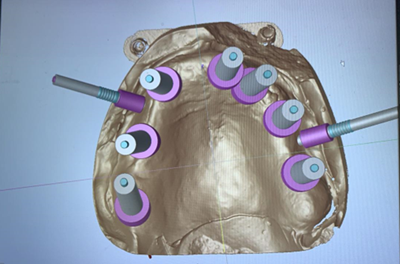

We chose the placement of 7 implants type Straumann without immediate loading (Figure 12). The type of the surgical guide is mucosa soft tissue supported with fixation by pins. A Flapless surgery without Bone regeneration, and a sinus Graft on 28.

Step 7: Production of the Printed Surgical Guide

In our case, we did indirect digital impressions by using a desktop scanner to convert a Vinyl Polysiloxane Impression Materials impression or a model into a digital impression. Once the maxillary, mandibular, and bite scan files (digital impressions) are ready, export and save them in the highest resolution on the computer in STL format.

Surgical Guide Design

Designing the Surgical Guide is the second step in this workflow. Designing can be done either by using an outside provider, or it may be done in-house by the dentist.

Surgical Guide Fabrication

The appliance can be printed as soon as its design is complete.

Assembly and Sterilization

This stage involves ensuring that the surgical guide is polished, the sleeve is correctly fitted onto the surgical guide, and the surgical guide is completely sterilized.

Figure 17: Guide in progress.

Figure 18: Guide ready to print.

Figure 19: Guide printed with the sleeves and fixations pins placed.